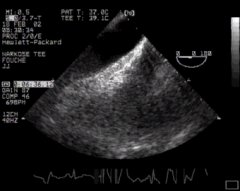

If we wish, we can view the aorta in long axis by rotating the biplane or multiplane probe through ninety degrees - 'DESC Aorta LAX':

CLICK FOR VIDEO: descending aorta lax view